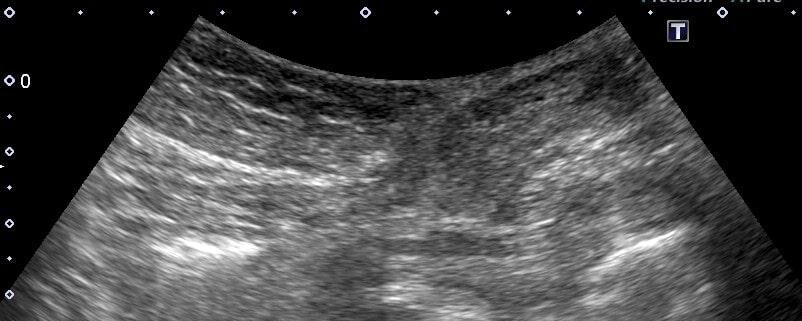

スキャンしましたが歳相応の石灰化のみ。瘤や解離はなさそうなので一安心。

- 腸拡張は認めない

微妙ですが、「腸拡張がない」という時点で絞扼性ではないと判断して良かったのかなとも。